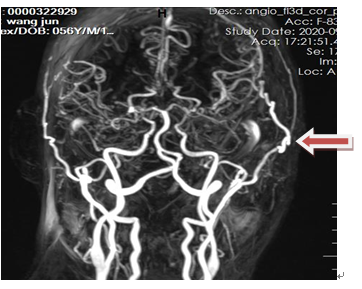

DSA:顱底煙霧狀血管形成(箭頭所示)。

術(shù)后第5天查MRA示:顳淺動(dòng)脈-大腦中動(dòng)脈吻合血管通暢(箭頭所示)。